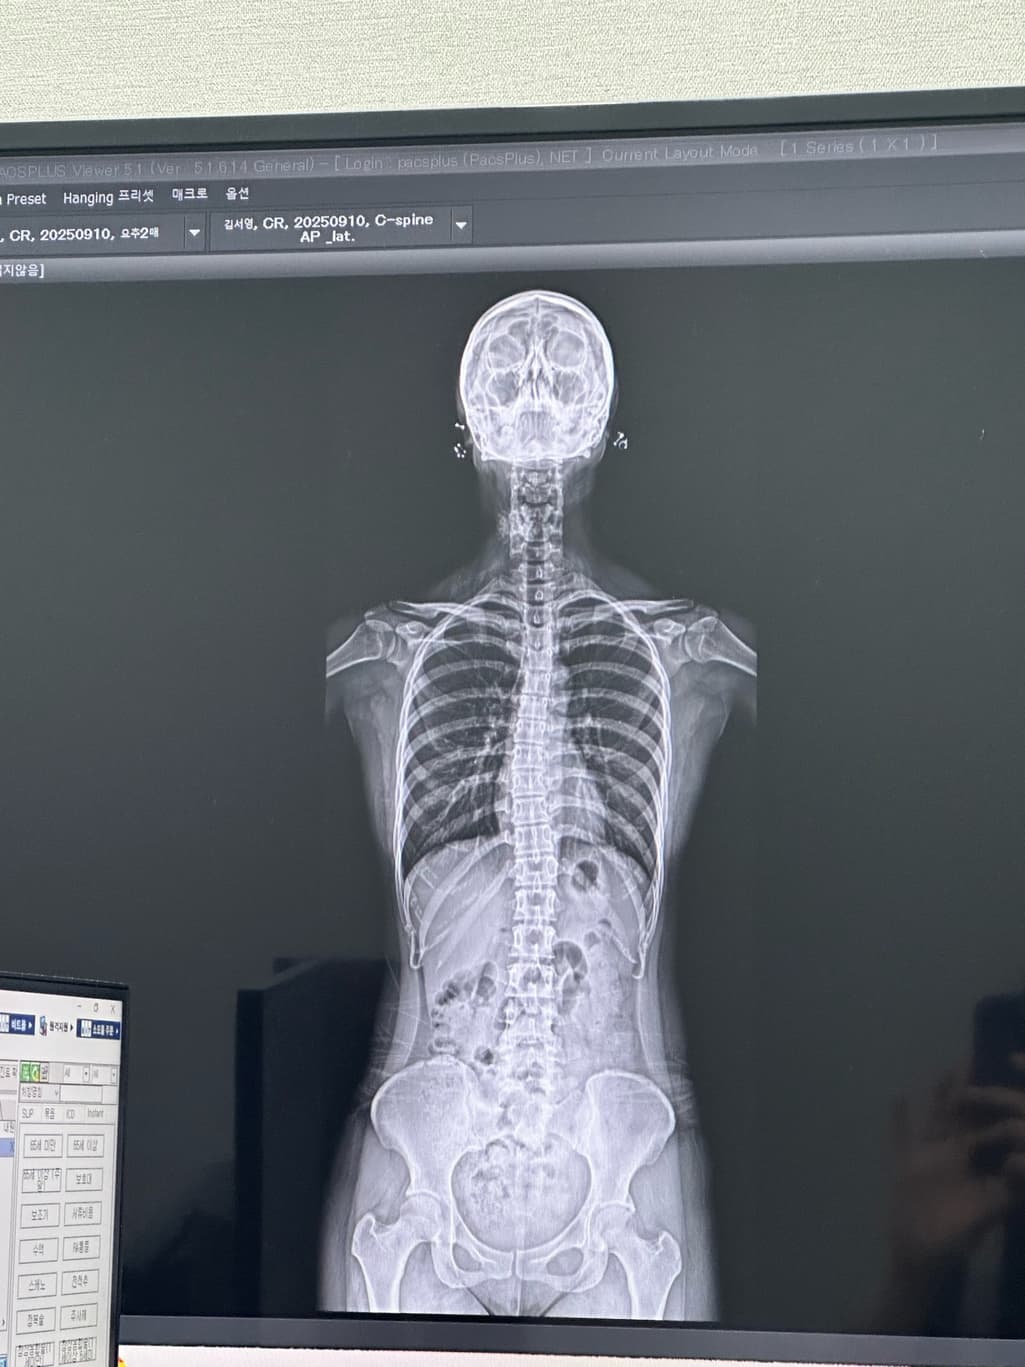

집에서 운동하면 휜 허리나 거북목이 다시 돌아올수 있을까요?? 집에서 허리운동해도될까요? 그리고 제가 허리디스크인지도 궁금합니다 까먹고 못물어봤어요 디스크사이에 공간이 있어야하는데 줄어들어잇다 하더라고요

사진상으로 볼때 골반불균형이 보이기는하지만 심한정도는아닌거같기때문에 치료를받으면서 운동과 스트레칭을 꾸준하게한다면 충분히 교정이가능할것으로보입니다

X-ray상으로 디스크를 정확하게 알 수는 없으며 척추체 사이가 간격이 좁아져 있다면 디스크 이상을 의심해볼 수 있습니다.

X-ray상 골반틀어짐, 척추측만증 등 전체적으로 신체 균형이 틀어져 있는 것으로 보이며 잘 못된 운동은 증상을 더 악화시킬 수 있기때문에 정형외과에서 진료받으시고 체형교정을 위한 도수치료를 받으시는 것이 도움이 되실 것입니다.